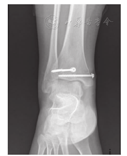

39例患者随访5~91个月,平均35个月。AOFAS评分系统评判结果为优27例,良10例,一般2例。患者踝关节稳定,抽屉及内外翻试验均阴性,无步态异常。患儿均能参加正常的体育活动。9例患者偶有运动后踝关节轻度疼痛。随访中患者均行X线复查。空心钉拔除后1年患儿均接受踝关节X线复查,无骨骺早闭病例(图3)。检查结果显示所有病例均骨性愈合,未发现关节面不平整现象,未发现双下肢不等长和踝关节畸形。39例患者伤口愈合良好,无伤口感染发生。全部病例中已有28例内固定物取出,其中1例术前发现空心钉折断,选用专用空心钻完整取出,未伤及骺板和关节面(图4)。

本组1例患儿术后6个月复查时发现其中一枚空心螺钉断裂,对于断钉,临床发生率低,主要原因包括:(1)为避免伤及骺板和关节面,选择了较细的空心钉。(2)留置时间过长。(3)患儿自我保护差,术后参与剧烈运动。如何避免?本研究经验:(1)尽量选择粗的空心钉。过骨骺的空心钉,选择骨骺厚度2/3直径的空心钉为宜。术中导针定位非常重要,避免伤及骺板和关节面。(2)留置时间不能过长,本组患儿一般选择术后4~6个月取出内固定。(3)术后健康宣教,避免剧烈运动,加强自我保护。如果出现断钉,应及早发现,此时断钉的断端移位小,便于导针插入,再用空心钻完整取出;反之取钉困难,可考虑不取。